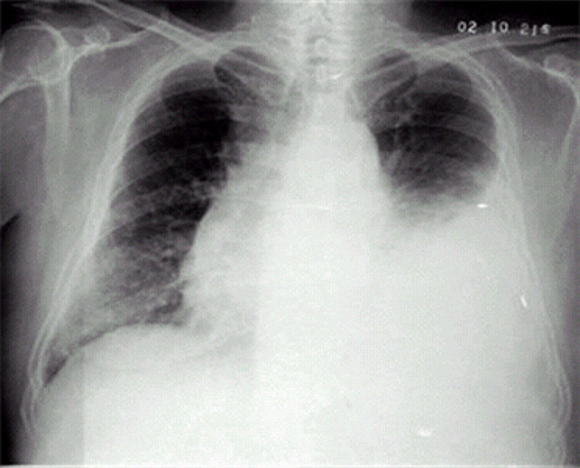

我們再來一題。第二題,看題。

有答案了麼?

沒錯,左側大量胸腔積液。看一下ChatGPT。

檢查還是一如既往的判斷準確,但是左右搞反了,胸片的左右是反的,我們看到的右側是病人的左胸,而且他雖然説出了正確答案胸腔積液,但畫蛇添足地加了個胸腔積氣,氣胸的表現可不是這樣的。